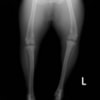

■ 症例20 ポメラニアン 8ヶ月 1.8kg

左右膝蓋骨脱臼 グレードⅢ

2ヶ月前から間欠的跛行が認められ、両膝の膝蓋骨脱臼整復術を行った。

手技は縫工筋及び内側広筋の解放、脛骨粗面の外側転位、滑車ブロック形造溝術、内外側関節包の縫縮を選択し実施した。

右側の膝蓋骨脱臼は上記手技で整復されたものの、左側はそれのみでは膝蓋骨が浮く様子が認められた。その為、PDS縫合糸にて膝蓋靱帯を1糸のみ縫合し、靱帯の縫縮を行った。

膝蓋骨脱臼は膝関節における膝蓋骨の内外側の脱臼と定義されるが、時として単純な内外の脱臼ではなく、膝蓋骨が大きく前方に浮き上がるように脱臼する場合がある。特にトイプードルやポメラニアンといった犬種に多く認められる。

内側脱臼に加えて前方への浮き上がりを矯正する為に、従来より脛骨粗面転移により膝蓋靭帯を外方と下方に引っ張り、固定する方法を選択する。膝蓋骨の前方への浮き上がりが軽度の場合は、従来法ではなく関節包の縫縮で対応していた。しかし、一部の症例で膝蓋骨の動きが悪くなり伸展機構が円滑に機能せずロボット様歩行になるケースがあった。

その為、膝蓋靭帯自体を縫縮する方法を採用した。この方法により、膝関節の伸展機構を妨げず膝蓋骨の軽度の浮きを矯正することが可能となった。

本症例の経過は良好である